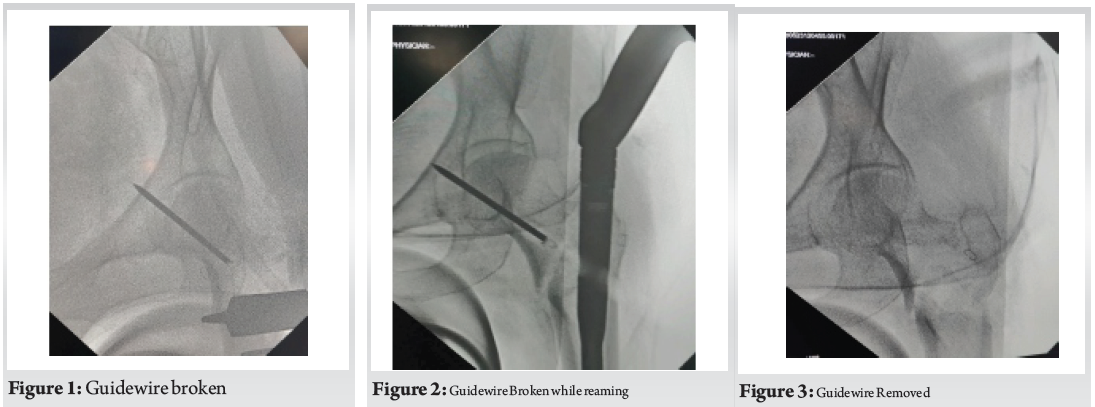

During cephalomedullary nailing, while reaming over the guide wire for the proximal lag screw, resistance was encountered followed by sudden loss of resistance. Fluoroscopic imaging revealed a broken guide wire lodged in the femoral neck (Fig. 1, 2). Attempts at removal with a pituitary rongeur were unsuccessful. (Fig. 3)